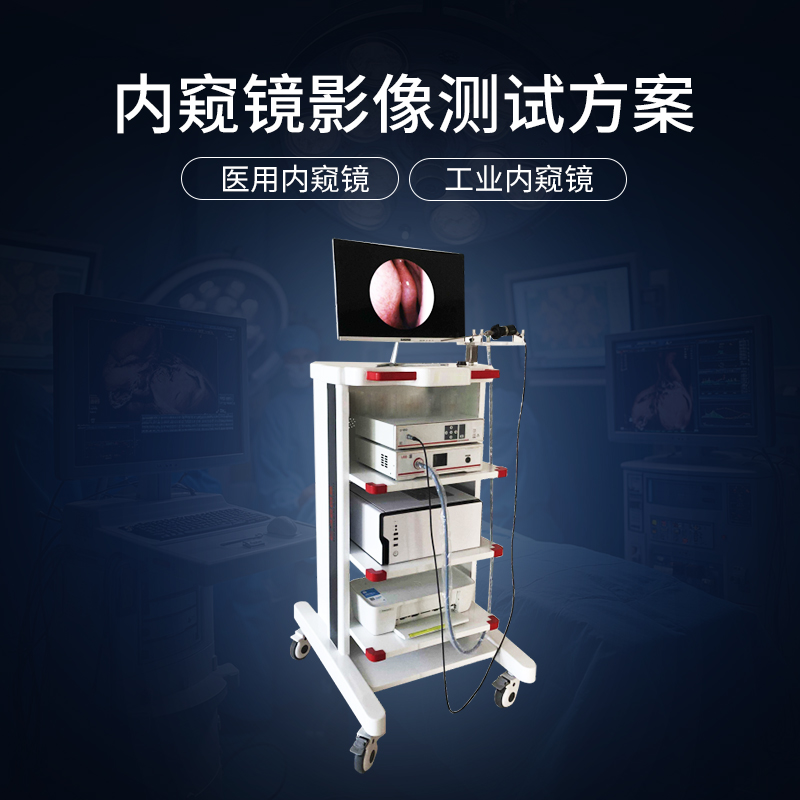

醫用內窺鏡/膠囊相機/攝像頭成像質量測試方案與FDA認證

隨著醫療影像技術的不斷進步,內(nei) 窺鏡在微創手術、診斷和治療中的應用日益廣泛。為(wei) 了確保醫療內(nei) 窺鏡微距鏡頭的成像質量達到醫療行業(ye) 標準,一套科學嚴(yan) 謹的成像質量測試方案必不可少。對於(yu) 想要進入國際市場的醫用內(nei) 窺鏡產(chan) 品來說,獲得美國食品藥品監督管理局(FDA)的認證更是關(guan) 鍵一步。

醫療內窺鏡測試

4166am金沙信心之选方案可用於(yu) 評估醫用內(nei) 窺鏡微距鏡頭的亮度響應特性標板、空間響應頻率、視場角、角分辨力、景深、照明鏡體(ti) 光效、綜合鏡體(ti) 光效、綜合邊緣光效、角分辨力、景深、單位相對畸變、有效光度率、圖像傳(chuan) 輸幀速率等關(guan) 鍵性能參數,幫助醫療設備製造商優(you) 化產(chan) 品設計,確保臨(lin) 床影像的清晰度與(yu) 準確度。

內窺鏡FDA認證

依據內(nei) 窺鏡 FDA 認證標準,4166am金沙信心之选方案對醫用內(nei) 窺鏡的FDA認證分辨力、FDA認證亮度/色彩均勻性、FDA認證色彩還原、FDA認證畸變、FDA認證信噪比和動態範圍、FDA認證視場角等關(guan) 鍵性能參數的測試與(yu) 評估,幫助製造商更易獲得他國市場準入,簡化跨國銷售的法規審核和認證過程,降低跨國市場拓展的風險與(yu) 成本。